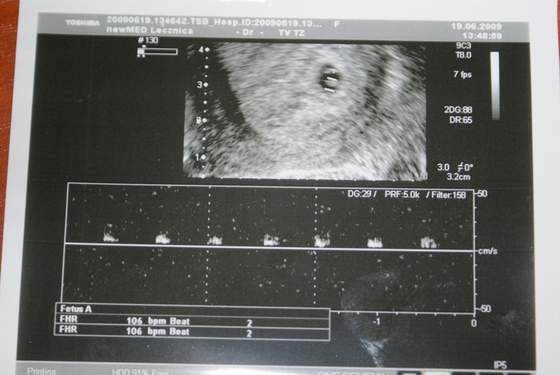

Dzisiaj byłam u ginka i ... moja druga Fasolka ma 4,3 mm i serduszko bije 106 razy na minutę. Mam cztery cudne zdjęcia i bez przerwy na nie patrzę.